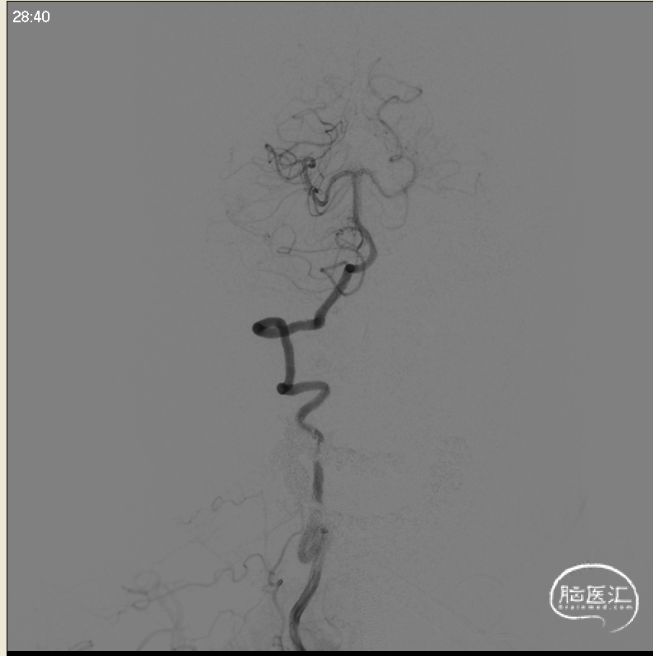

术前左侧侧位

术前左侧正位

术前右侧正位

术前右侧侧位

术前左椎侧位

术前左椎正位

术前右椎侧位

术前右椎侧位

术前工作位